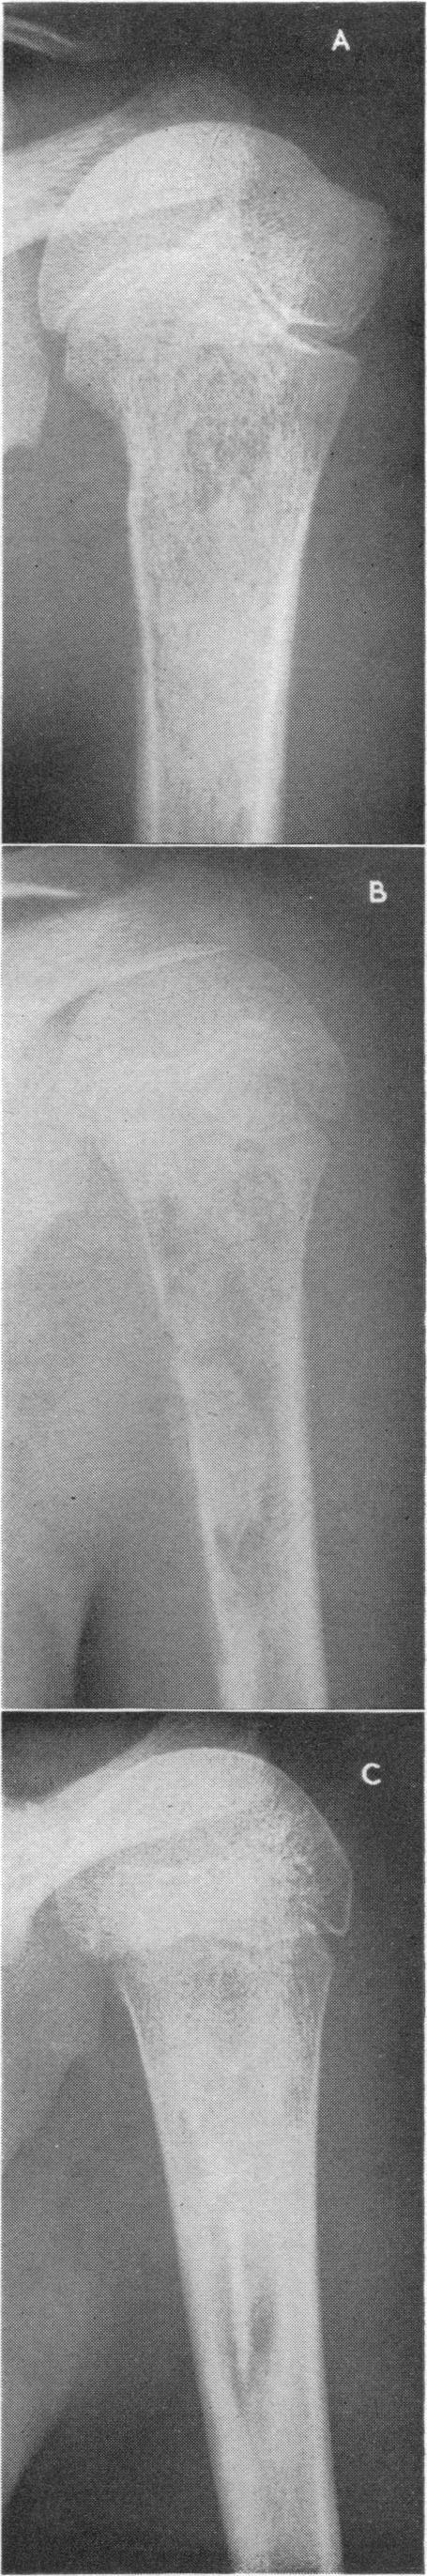

Place of surgery in early stages of acute osteomyelitis.

Br Med J. 1962 May 26;1(5290):1440-4. doi: 10.1136/bmj.1.5290.1440.